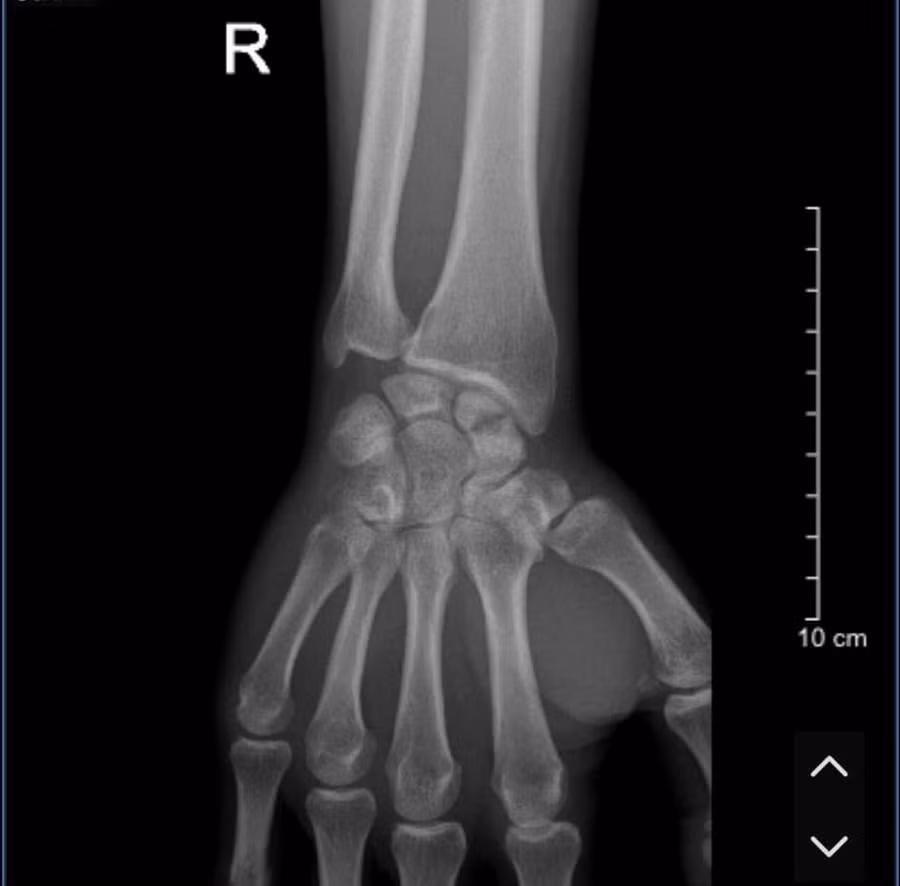

BS. Sơn khuyến cáo: "Những triệu chứng của gãy xương thuyền là đau, sưng, ấn đau vùng cổ tay, không có biến dạng rõ ràng, vì thế mà gãy xương thuyền có thể nhầm lẫn với bong gân cổ tay nên bác sĩ phải hỏi bệnh sử về cơ chế gãy chấn thương, khám thực thể kết hợp chụp phim Xquang, CT, MRI để đánh giá những điểm khác nhau của gãy xương thuyền.

Gãy xương thuyền cần được quan tâm đúng mức, tránh bỏ sót thương tổn, có chỉ định can thiệp đúng và hợp lý để tránh bỏ sót thương tổn".